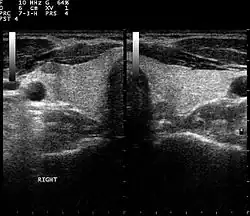

Muscoesqueleto

Tendones, músculos, nervios, ligamentos, masas de tejidos blandos y superficies óseas. Es una alternativa a la radiografía en la detección de fracturas de muñeca, codo y hombro para pacientes de hasta 12 años.

Endocrinología, laringología

La mayoría de las estructuras del cuello, incluyendo las glándulas tiroides y paratiroides, los ganglios linfáticos y las glándulas salivales, se visualizan bien mediante ultrasonidos de alta frecuencia con imágenes de alta calidad. La ecografía es una modalidad de imagen con especial incidencia en lesiones de tiroideas.[19]